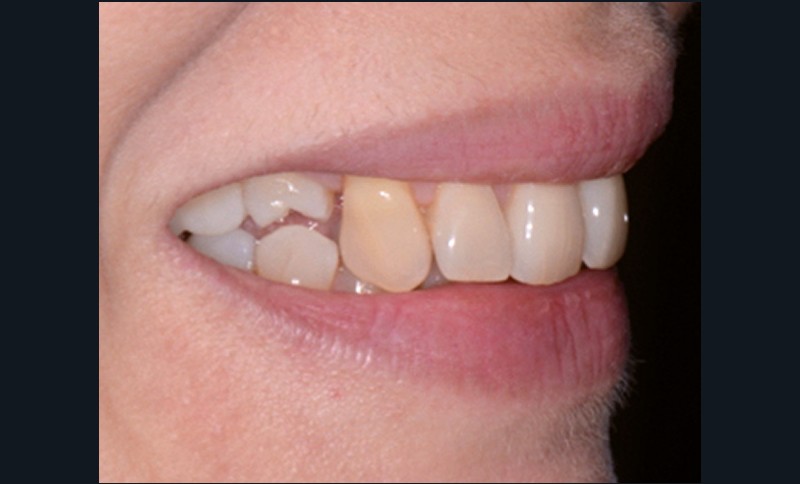

Sur les figures 1a et b, les trois étages de la face sont équilibrés. Le sourire met en évidence une légère bascule du plan d’occlusion.

Les muscles orbiculaires se contractent lorsque les lèvres sont jointives. Le sourire est spontané, large et les lèvres sont charnues. La courbe du sourire est satisfaisante de 12 à 22 puis les dents rentrent, disparaissent de face et apparaissent plus hautes sur le sourire de trois-quarts. Les incisives maxillaires sont bien placées par rapport à la lèvre inférieure (fig. 3).

Fig. 1 – Photographies exobuccales de face au repos (a) et lors du sourire (b), février 2016. Visage équilibré aux trois étages de même hauteur. Le sourire est…